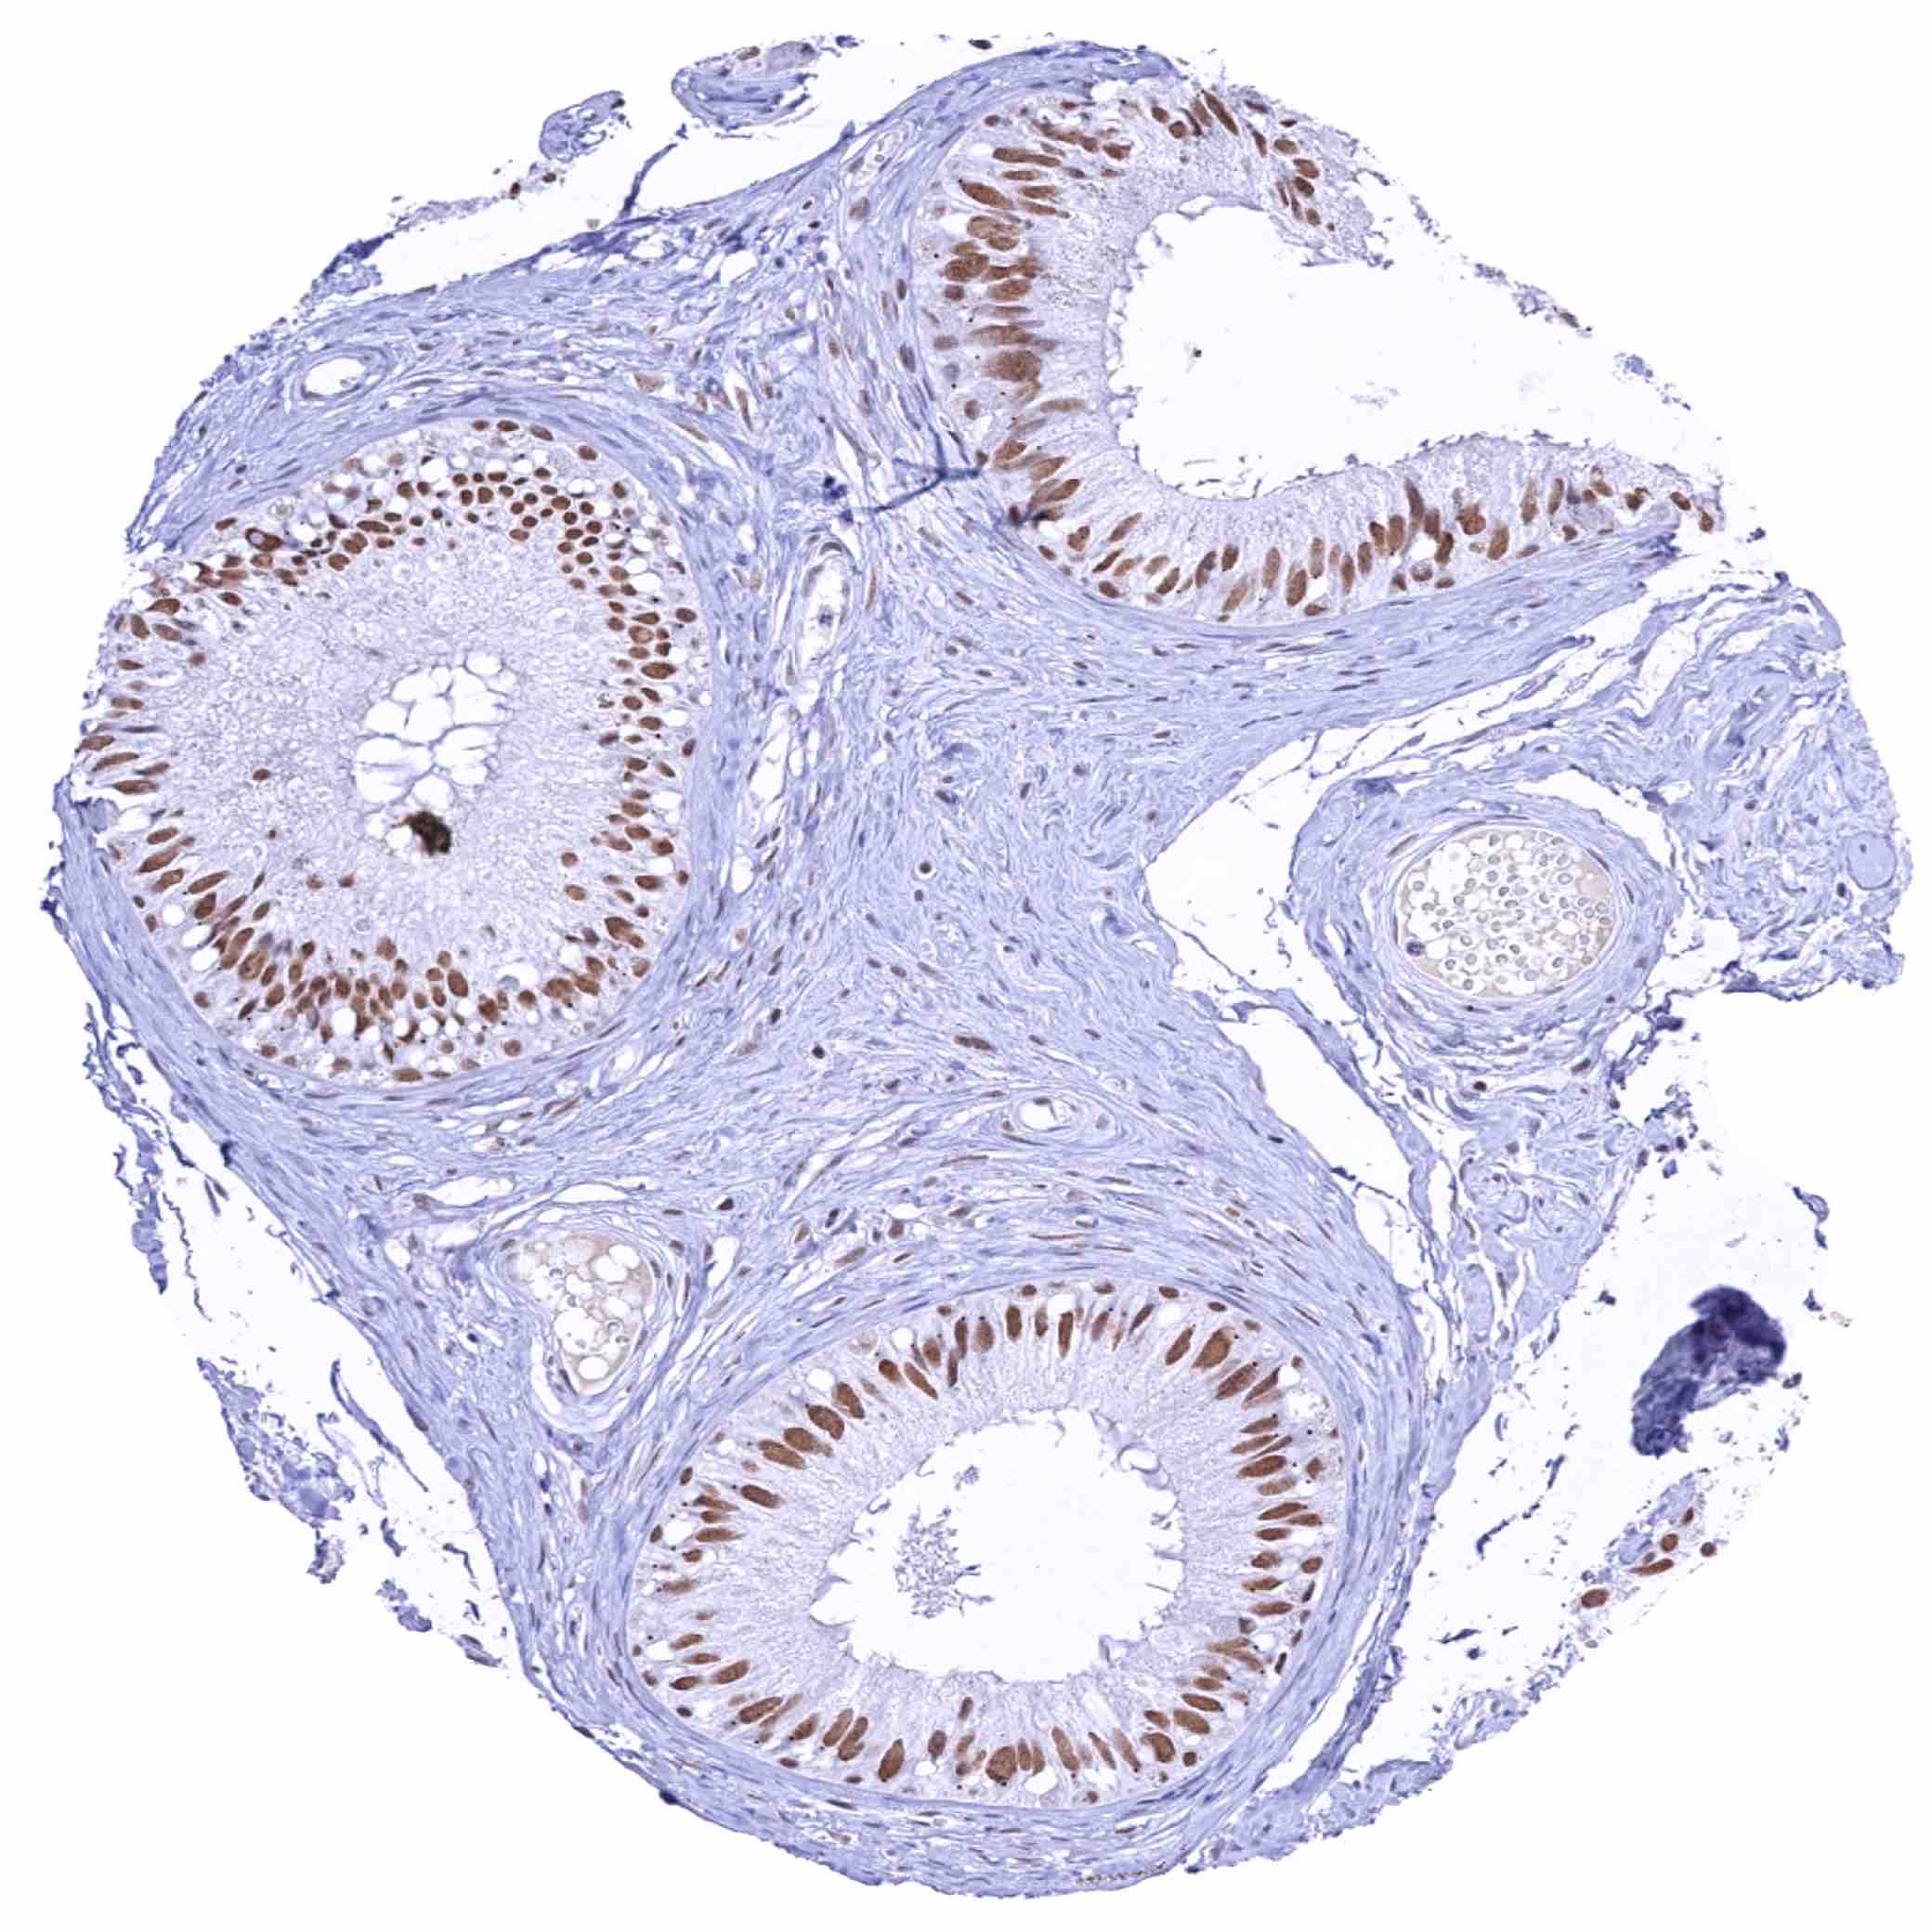

Prostate – Moderate nuclear KDM6A staining of all epithelial cells